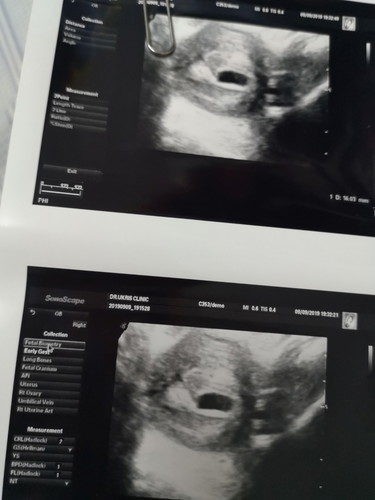

ท้องประมาณ 6 week คุณหมอซาวด์แล้วขึ้นแค่ถุงน้ำคร่ำ ยังไม่เจอน้อง ปกติใช่มั้ยคะ

ซาวด์ทางหน้าท้องหรือช่องคลอดคะแม่ ถ้าทางหน้าท้อง ถ้าตัวอ่อนยังเล็กมากๆ หรือเป็นคนหน้าท้องหนา อาจจะยังไม่เห็นค่ะแม่ ทางช่องคลอดจะพอมีลุ้นมากกว่าค่ะ ทั้งนี้เป็นไปได้ว่า อายุครรภ์อาจจะน้อยกว่าที่นับ เพราะไข่อาจจะตกช้ากว่ากำหนด ตัวอ่อนยังเล็กมากอยู่ จึงยังไม่พบ ก็เป็นได้ค่ะแม่ ทานโฟลิคทุกวัน พักผ่อนเยอะๆ นะคะ ซาวด์ครั้งหน้าอาจจะได้เจอกันแล้วจ้า

Đọc thêmปกติจ้า บ้านนี้ก็ซาวตอน6wค้ะใม่เจอน้องเจอแต่ถุงตั้งครรภ์แต่แม่ตัดสินใจฝากเรยค้ะ หมอนัดอีก3wต่อมาเป็นตัวมาเรยค่ะมีแขนมีขามีหัวใจ รอหน่อยน้ะค้ะแม่

ปกตินะคะ ซาวด์ครั้งแรกผ่านหน้าท้องไม่เห็น ทางช่องคลอดเห็นถุงเป็นวงรี ตกใจมาก แต่มาเจอหัวใจตอน 6wk ค่ะ ตอนนี้ 13 wk ดุ๊กดิ๊กละค่า

ซาวน์ผ่านทางช่องคลอดอาจจะเห็นได้ชัดกว่านะคะ บ้านนี้ซาวน์ตอน 6w เหมือนกันค่ะ เห็นหัวใจน้องกับได้ฟังคลื่นหัวใจค่ะ

ของบ้านนี้ 6 วีค อัลตร้าซาวน์ผ่านช่องคลอด เจอน้องแล้ว เห็นคลื่นหัวใจแล้วด้วยค่ะ แต่หมอยังไม่ได้ให้ฟังเสียง

ซาวด์ผ่านหน้าท้อง ยังไม่เห็นค่ะแม่ บ้านนี้มีภาวะแท้งคุกคาม ตอน6 Weeks คุณหมอซาวด์ผ่านช่องคลอดถึงเจอค่ะ

บ้านนี้6วีคยังไม่เห็นน้องค่ะ หมอเลยซาวผ่านช่องคลอดให้ดูน้องยังเล็กอยู่ค่ะนัดอีกที10ต.ค ค่ะ